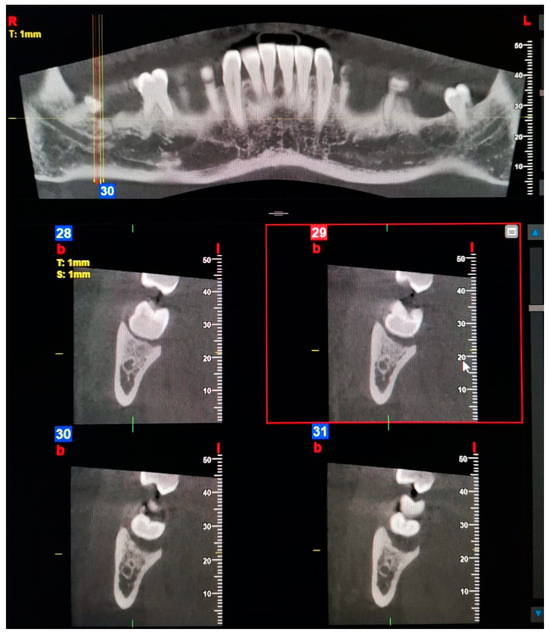

Examples of images considered positive for BMC and TMC are shown in Figure 1, Figure 2, Figure 3, Figure 4, Figure 5, Figure 6 and Figure 7. Regarding the distribution among patients, 36 subjects (15.13%) showed at least one BMC, 12 (5.04%) bilaterally, while 2 subjects (0.84%) showed a TMC. Among patients with cases considered positive for BMC, 21 were women, accounting for 8.82% of the total studied population and 14.89% of female patients overall. On the other hand, 15 BMC patients were men, accounting for 6.30% of the whole sample and 15.4% of men in the study. Considering the hemi-mandibles, BMC appeared in 9.87% of images, while TMC only appeared in 0.42%. The Patient group that was positive for BMCs had a mean age of 34 ± 13.30, while the group that was positive for TMCs presented a mean age of 43 ± 19.8. Pearson’s Chi-Square test was not significant; no association was found between gender and the prevalence of mandibular canals.

Figure 1. Panoramic view and transverse section of a bilateral Type 1—Retromolar (bifid mandibular canals) BMC. l, lingual. b, buccal. T, thickness. S, section.